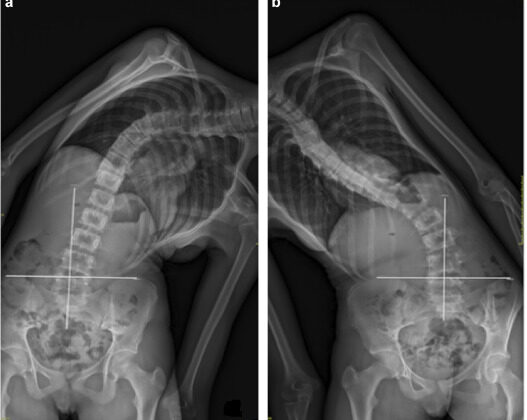

مرونة العمود الفقري تعني قدرة العمود على الانحناء أو التمدد قبل الجراحة. ببساطة، كلما كان العمود أكثر مرونة، كان من الأسهل تصحيح الانحناء أثناء الجراحة. يقيس الأطباء المرونة عادةً من خلال صور الأشعة أثناء الانحناء أو السحب، وتُعتبر هذه القياسات أساسية لتخطيط العملية وتوقع النتائج.

يقوم الأطباء بعمل أشعة خاصة لقياس مرونة الانحناء، وتُظهر مدى قدرة العمود الفقري على التكيف مع التغيرات أثناء الجراحة. بناءً على هذه المعلومات، يختار الطبيب: